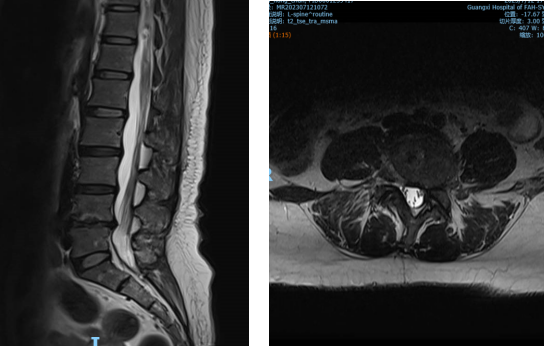

▲②术前MRI片

“医生,我这半年来腰痛的厉害,右腿现在又痛又麻,走路都困难,有什么办法处理吗?”在骨科诊室,患者谭阿姨(化名)苦恼地说道。捆绑调教 骨科脊柱外科专业专家欧裕福副主任医师详细询问谭阿姨病史,并为她安排了细致的检查,最终诊断为腰椎管狭窄症+腰椎滑脱症。

结合谭阿姨下腰部明显压痛、右下肢疼痛及活动障碍等症状,骨科脊柱外科团队经过多次术前讨论,并联合麻醉手术中心团队,为谭阿姨制定了个性化的诊疗方案,决定运用经皮内镜下腰椎减压融合技术为患者进行治疗。